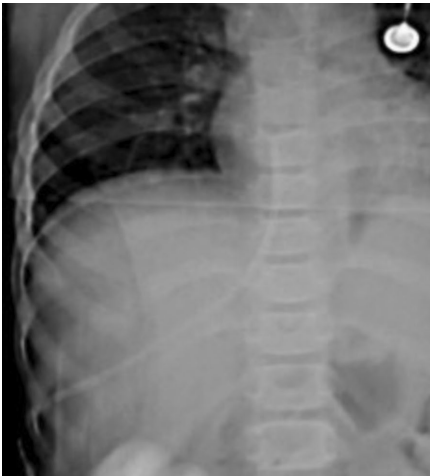

经肝导管置入:如图3所示,经肋间入路穿刺中肝静脉,导管经皮下隧道引出至腋中线。术后X线(图5)需确认导管位置。